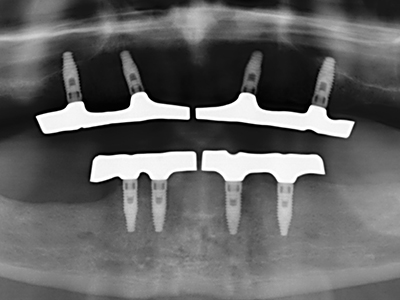

When surgical procedures are performed on bone in the immediate vicinity of sensitive structures such as blood vessels or nerves, rotary instruments pose a significant risk of iatrogenic injury. Piezoelectric devices can be helpful for preparation of bone covers and removal of hard tissue close to nerves, particularly for exposure of nerves after iatrogenic injury but also during nerve lateralization for resective and reconstructive procedures or implant placement (Fig. 17-20). Light contact between the piezotip and the nerve does not generally result in damage but proceeding incautiously with saw-like motions or attachments where a residual bone substrate remains may cause temporary or even permanent nerve damage. However, the risk of damage is considered to be substantially lower than when using saws or milling instruments (Pereira, Gealh et al. 2014).

As shown in the past, basically any bone surgery procedure represents a possible indication for piezo surgery. Thus preparation of the mobile segment in distraction osteogenesis (Fig. 23-25) and sandwich osteotomy uses special attachments without endangering the blood supply to the crestal section, which is essential for the success of both techniques (Gonzalez-Garcia, Diniz-Freitas et al. 2008).

For removal of an implant, a vestibular bone cover that is replaced after removal of the implant screw can be prepared to retain the contour of the alveolar ridge.

There are additional applications in sinus surgery. Pathologies and foreign bodies can be removed from the sinus after concentric preparation of a generally trapezoid bone cover in the facial sinus wall. The bone cover is repositioned on conclusion of the intra-antral operation component and secured by wedging or adaptive sutures to prevent dislocation.